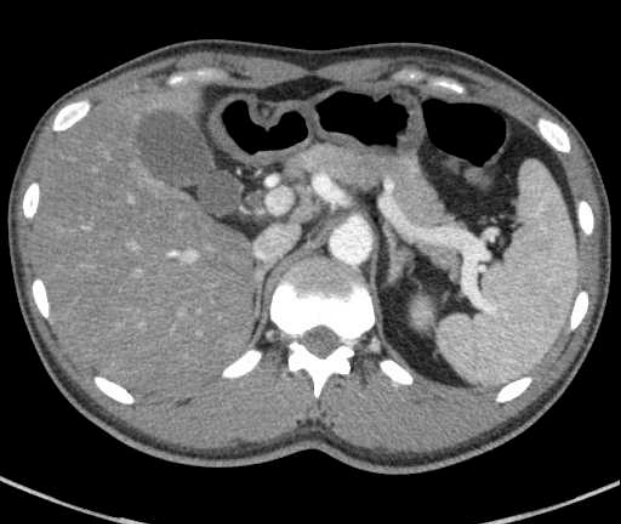

Figure 1.

Computed tomography at another hospital showed no hepatobiliary tract abnormalities or gall bladder wall edema.